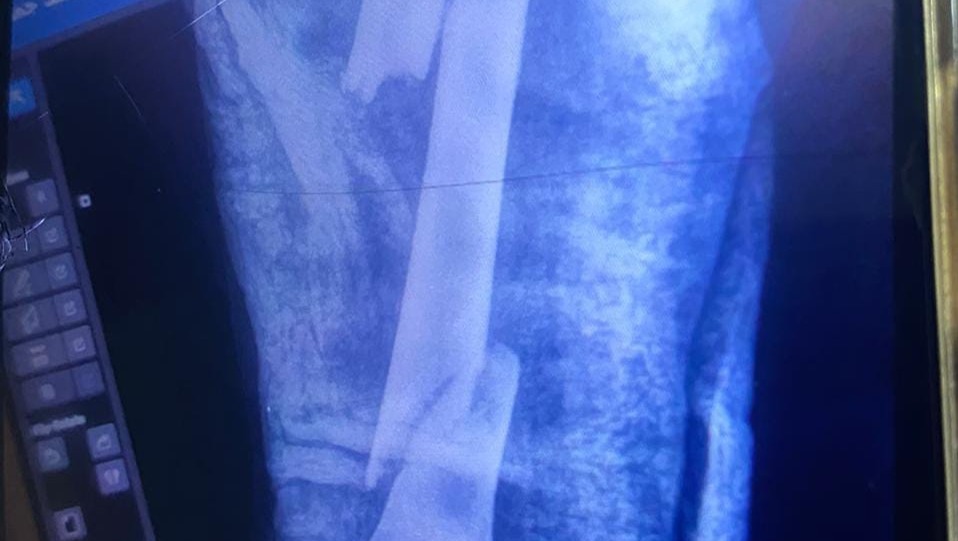

The surgery he did in February was because his leg got infected from the inside. And the last surgery he did in April was for the second broken bone, the doctors had put internal pins in the bone.

The Internal Pins

He needs to redo his platen because the surgery wasn't successful, as there is a lack of medical capabilities and supplies.